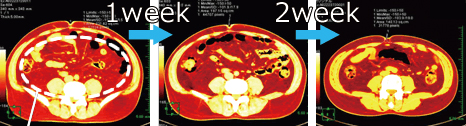

MRI機器による計測では 内臓脂肪の 消滅を確認!! ![]() 驚異的な 脂肪減少を記録!! さらに ▼ ▼ ▼ 毛細血管に入り込んだ ミクロの脂肪まで 溶解するから 血液の質が変化し ![]() ドロドロ血液から サラサラ血液になることで ↓↓↓ 代謝がUP!! ![]() 蓄積された 頑固な脂肪が 細胞レベルで減少!! |